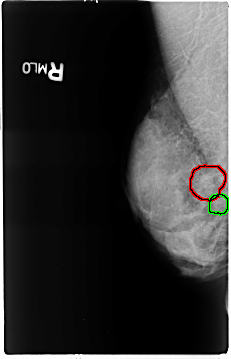

ics_version 1.0 filename B-3120-1 DATE_OF_STUDY 16 11 1994 PATIENT_AGE 50 FILM FILM_TYPE REGULAR DENSITY 4 DATE_DIGITIZED 25 2 1998 DIGITIZER LUMISYS LASER SEQUENCE LEFT_CC LINES 4624 PIXELS_PER_LINE 2976 BITS_PER_PIXEL 12 RESOLUTION 50 NON_OVERLAY LEFT_MLO LINES 4632 PIXELS_PER_LINE 2960 BITS_PER_PIXEL 12 RESOLUTION 50 NON_OVERLAY RIGHT_CC LINES 4616 PIXELS_PER_LINE 2960 BITS_PER_PIXEL 12 RESOLUTION 50 OVERLAY RIGHT_MLO LINES 4656 PIXELS_PER_LINE 2992 BITS_PER_PIXEL 12 RESOLUTION 50 OVERLAY |

FILE: B_3120_1.RIGHT_MLO.OVERLAY TOTAL_ABNORMALITIES 2 ABNORMALITY 1 LESION_TYPE CALCIFICATION TYPE PUNCTATE-PLEOMORPHIC DISTRIBUTION CLUSTERED ASSESSMENT 4 SUBTLETY 3 PATHOLOGY BENIGN TOTAL_OUTLINES 1 BOUNDARY ABNORMALITY 2 LESION_TYPE CALCIFICATION TYPE PUNCTATE-PLEOMORPHIC DISTRIBUTION CLUSTERED ASSESSMENT 4 SUBTLETY 3 PATHOLOGY BENIGN TOTAL_OUTLINES 1 BOUNDARY |